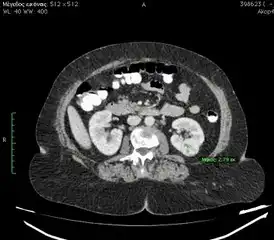

Η διάγνωση πραγματοποιείται με αξονική τομογραφία μετά τη χορήγηση ενδοφλέβιου σκιαγραφικού. Η πρόσληψη του σκιαγραφικού από τον όγκο είναι χαρακτηριστική της νόσου. Η αξονική τομογραφία (CT) μας δίνει πληροφορίες για το μέγεθος του όγκου, πιθανή έξωνεφρική επέκταση, τη συμμετοχή ή μη του σύστοιχου επινεφριδίου, ύπαρξη λεμφαδένων και την κατάσταση του άλλου νεφρού. Οι όγκοι του νεφρού μπορούν να διαχωριστούν βάσει της εικόνας τους στην CT. Οι όγκοι μπορούν να είναι συμπαγείς ή κυστικοί. Για την αξιολόγηση των δεύτερων χρησιμοποιείται το σύστημα Bosniak.